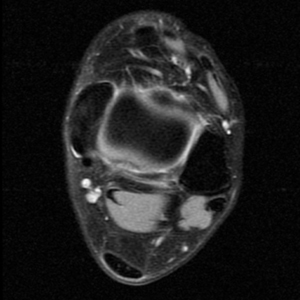

Coronal Oblique T1

Coronal Oblique PD FSE fat sat or GRE

The coronal oblique T1 sequence follows the tendons of the ankle around the malleolar turns and also evaluates the medial ankle ligaments.

The coronal oblique PD fat suppressed sequence follows the tendons of the ankle around the malleolar turns and is particularly important in evaluation of the Posterior tibialis tendon.